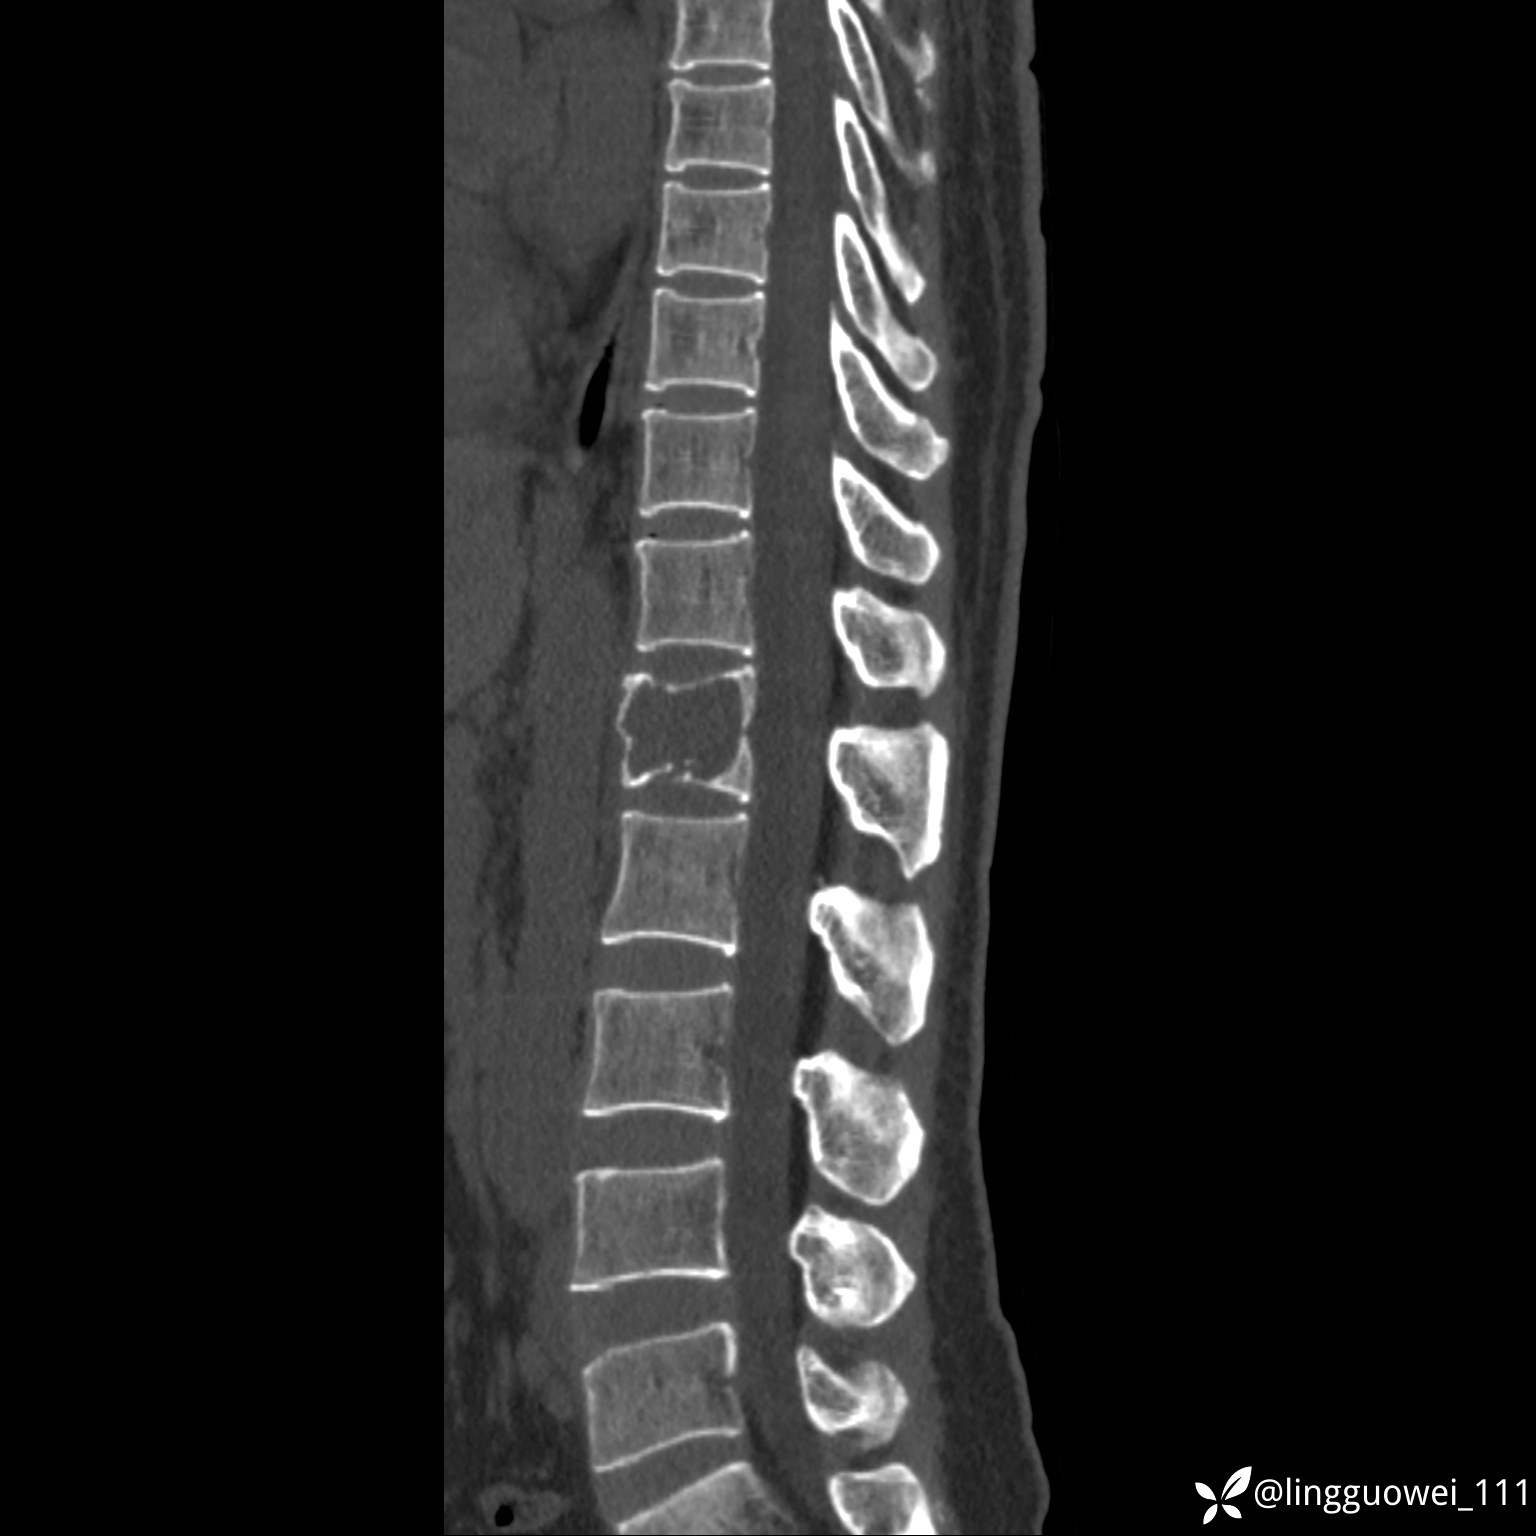

病例女,39岁,腰痛来诊,只有CT可能要鉴别诊断,而MR可以定性吗?

患者性别:女

患者年龄:39岁

主诉:腰痛